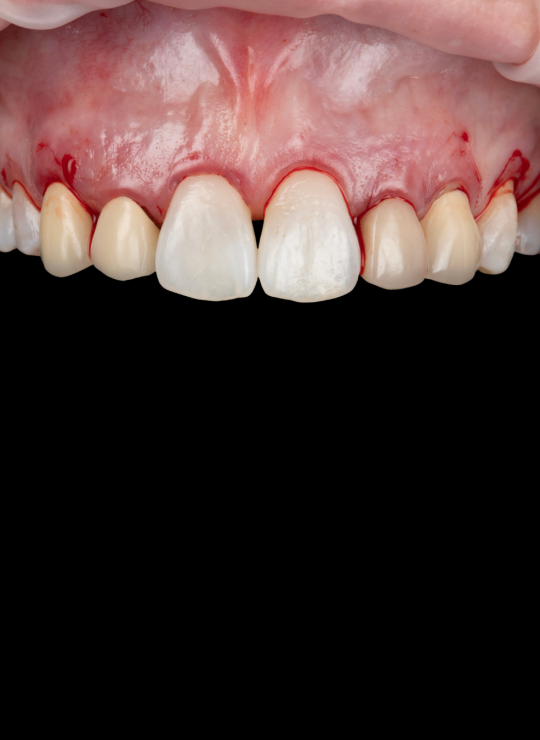

Surgical techniques for aesthetic crown lengthening: flap design, bone recontouring, and suturing

Management of altered passive eruption

Case demonstrations: gummy smile correction, uneven gingival margins, anterior restorative integration (veneers, crowns)

Surgical techniques for posterior crown lengthening: flap design modifications, osseous recontouring, suturing